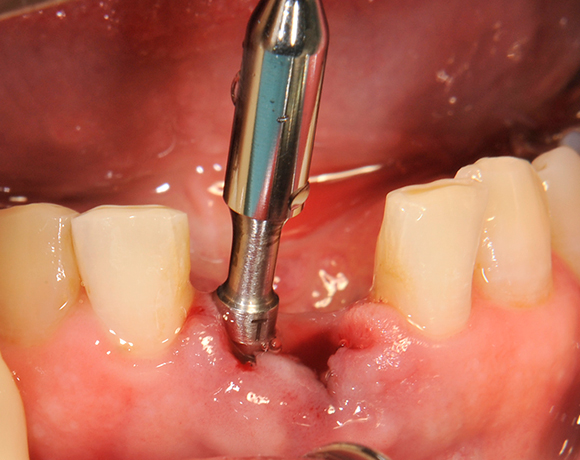

Die Keramikimplantate der Fa. Dentalpoint lassen sich auch zur Sofortimplantation verwenden. Das bedeutet, dass nach Extraktion nicht beherdeter Zähne direkt die Implantate gesetzt werden können.

Im vorliegenden Patientenfall wurden die beiden nicht erhaltungswürdigen, mittleren Unterkieferschneidezähne durch zwei Vollkeramikimlpantate ersetzt.